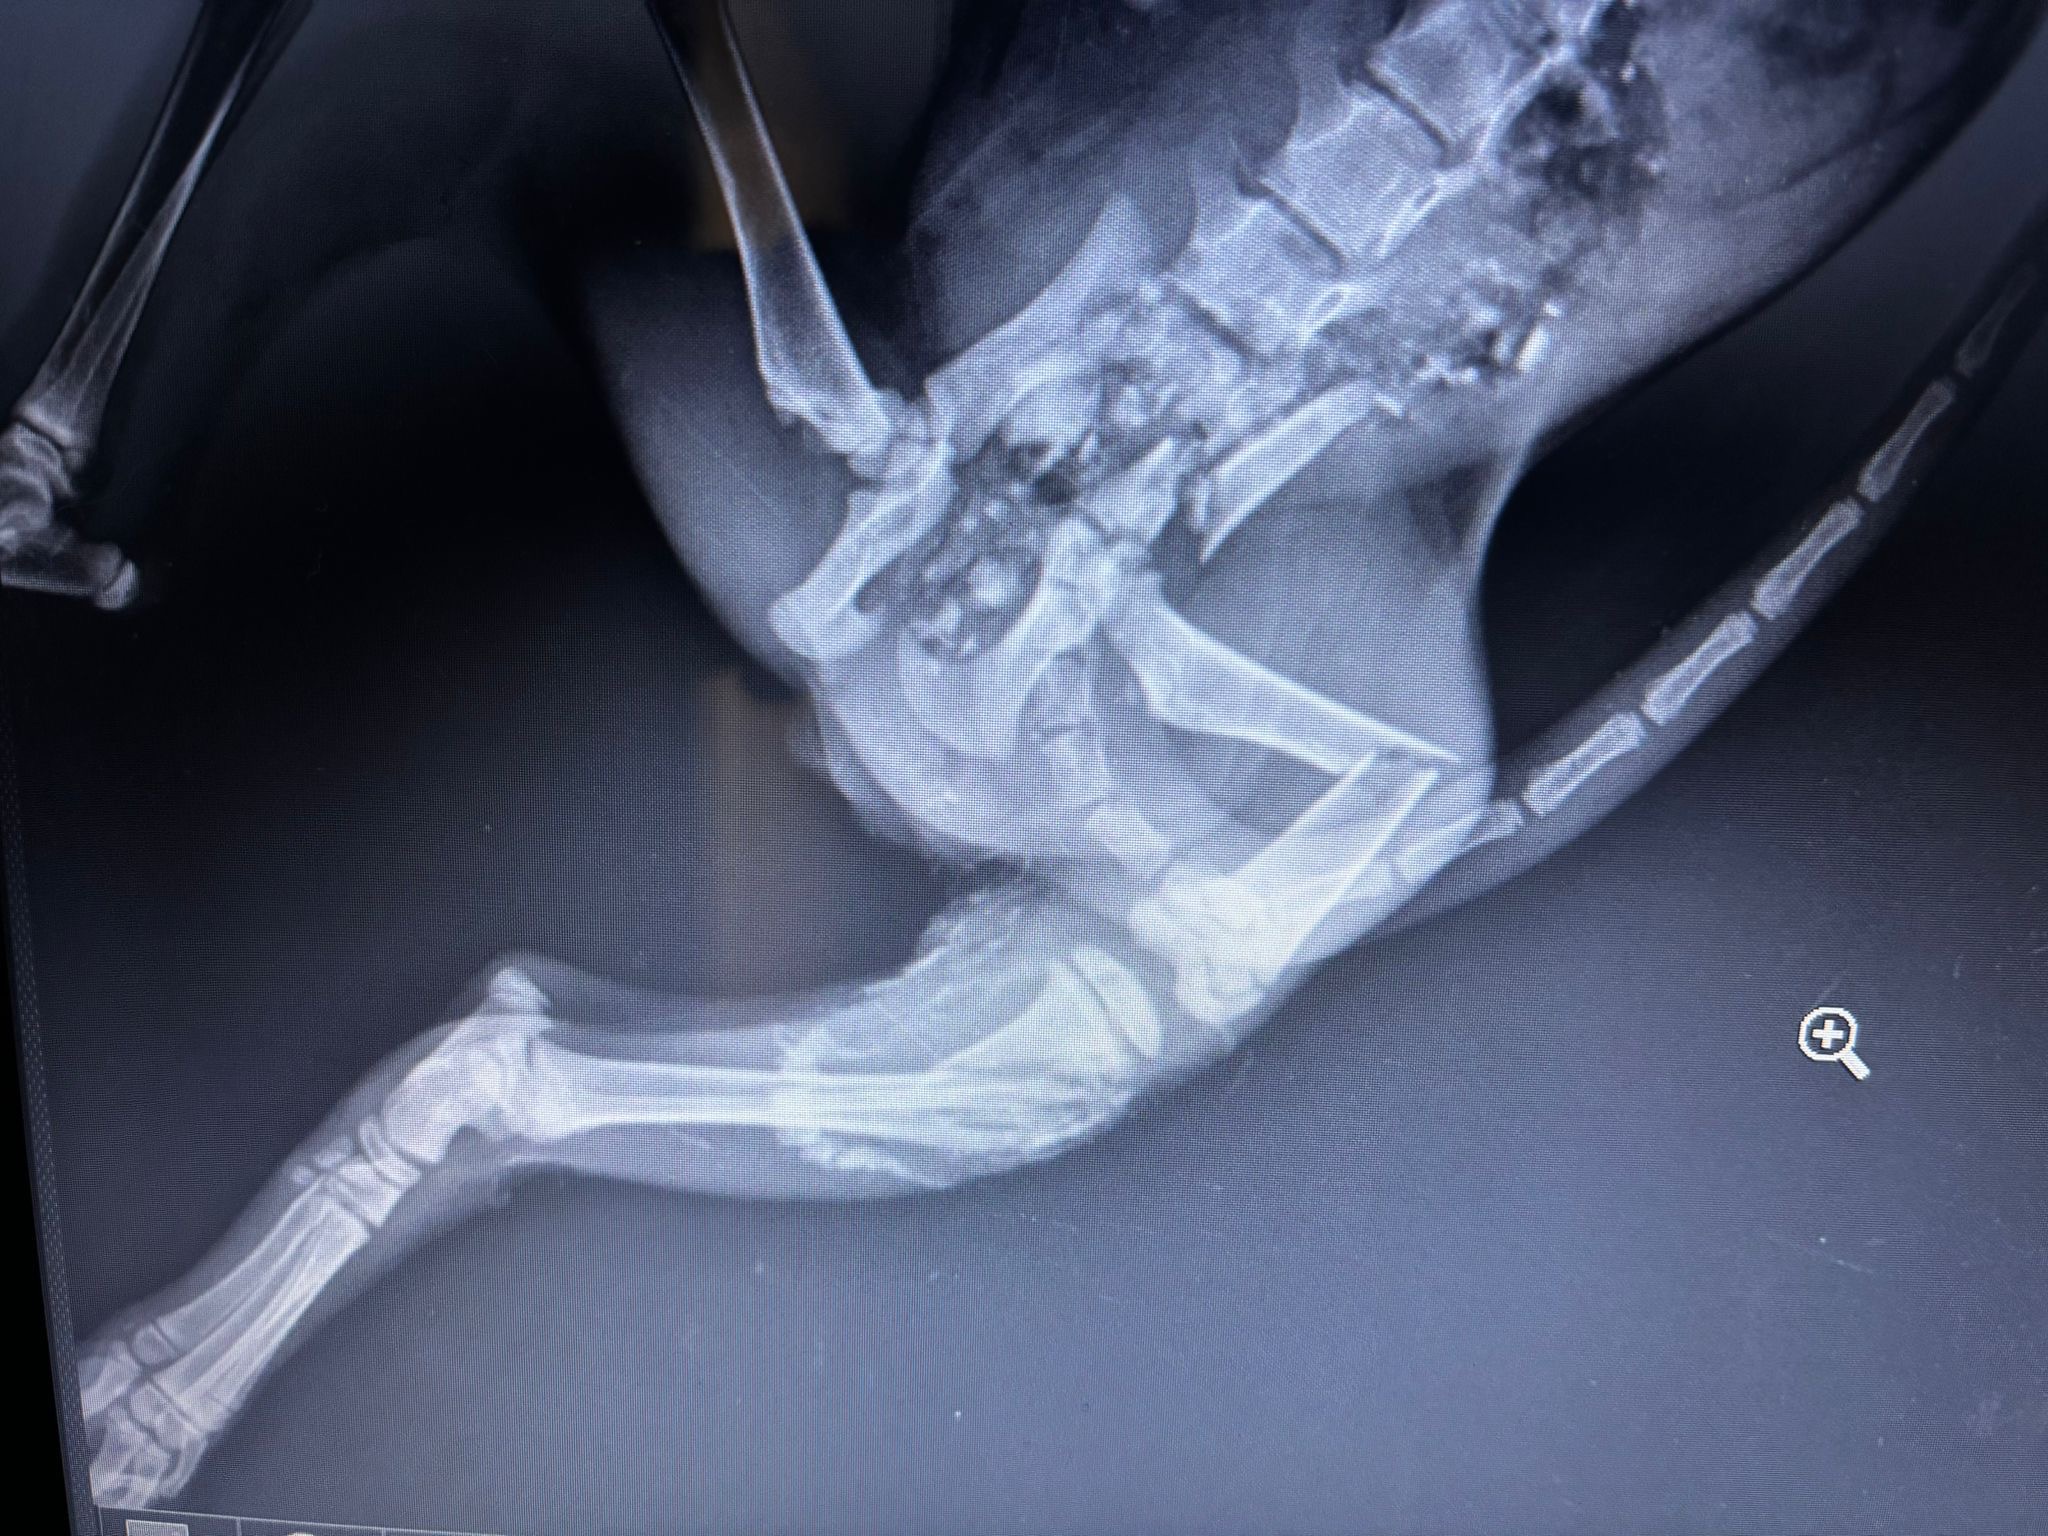

A stray cat, still a baby, was hit by a motorcycle, and the driver abandoned him in a corner and ran away. We saw the cat by chance and immediately took it to the vet. he had lost a lot of blood. It has fractures in its spinal cord and legs. He has implants in its spinal cord. he hasn't been operated on for his legs yet. his legs may need to be amputated. We expect your financial support during this operation. Afterward, we will find him a home with a warm and loving family. Thank you very much. I, Ceyda Arslan, will collect the donations, and when we reach the target amount, I will send the money to the veterinarian. Thank you very much.